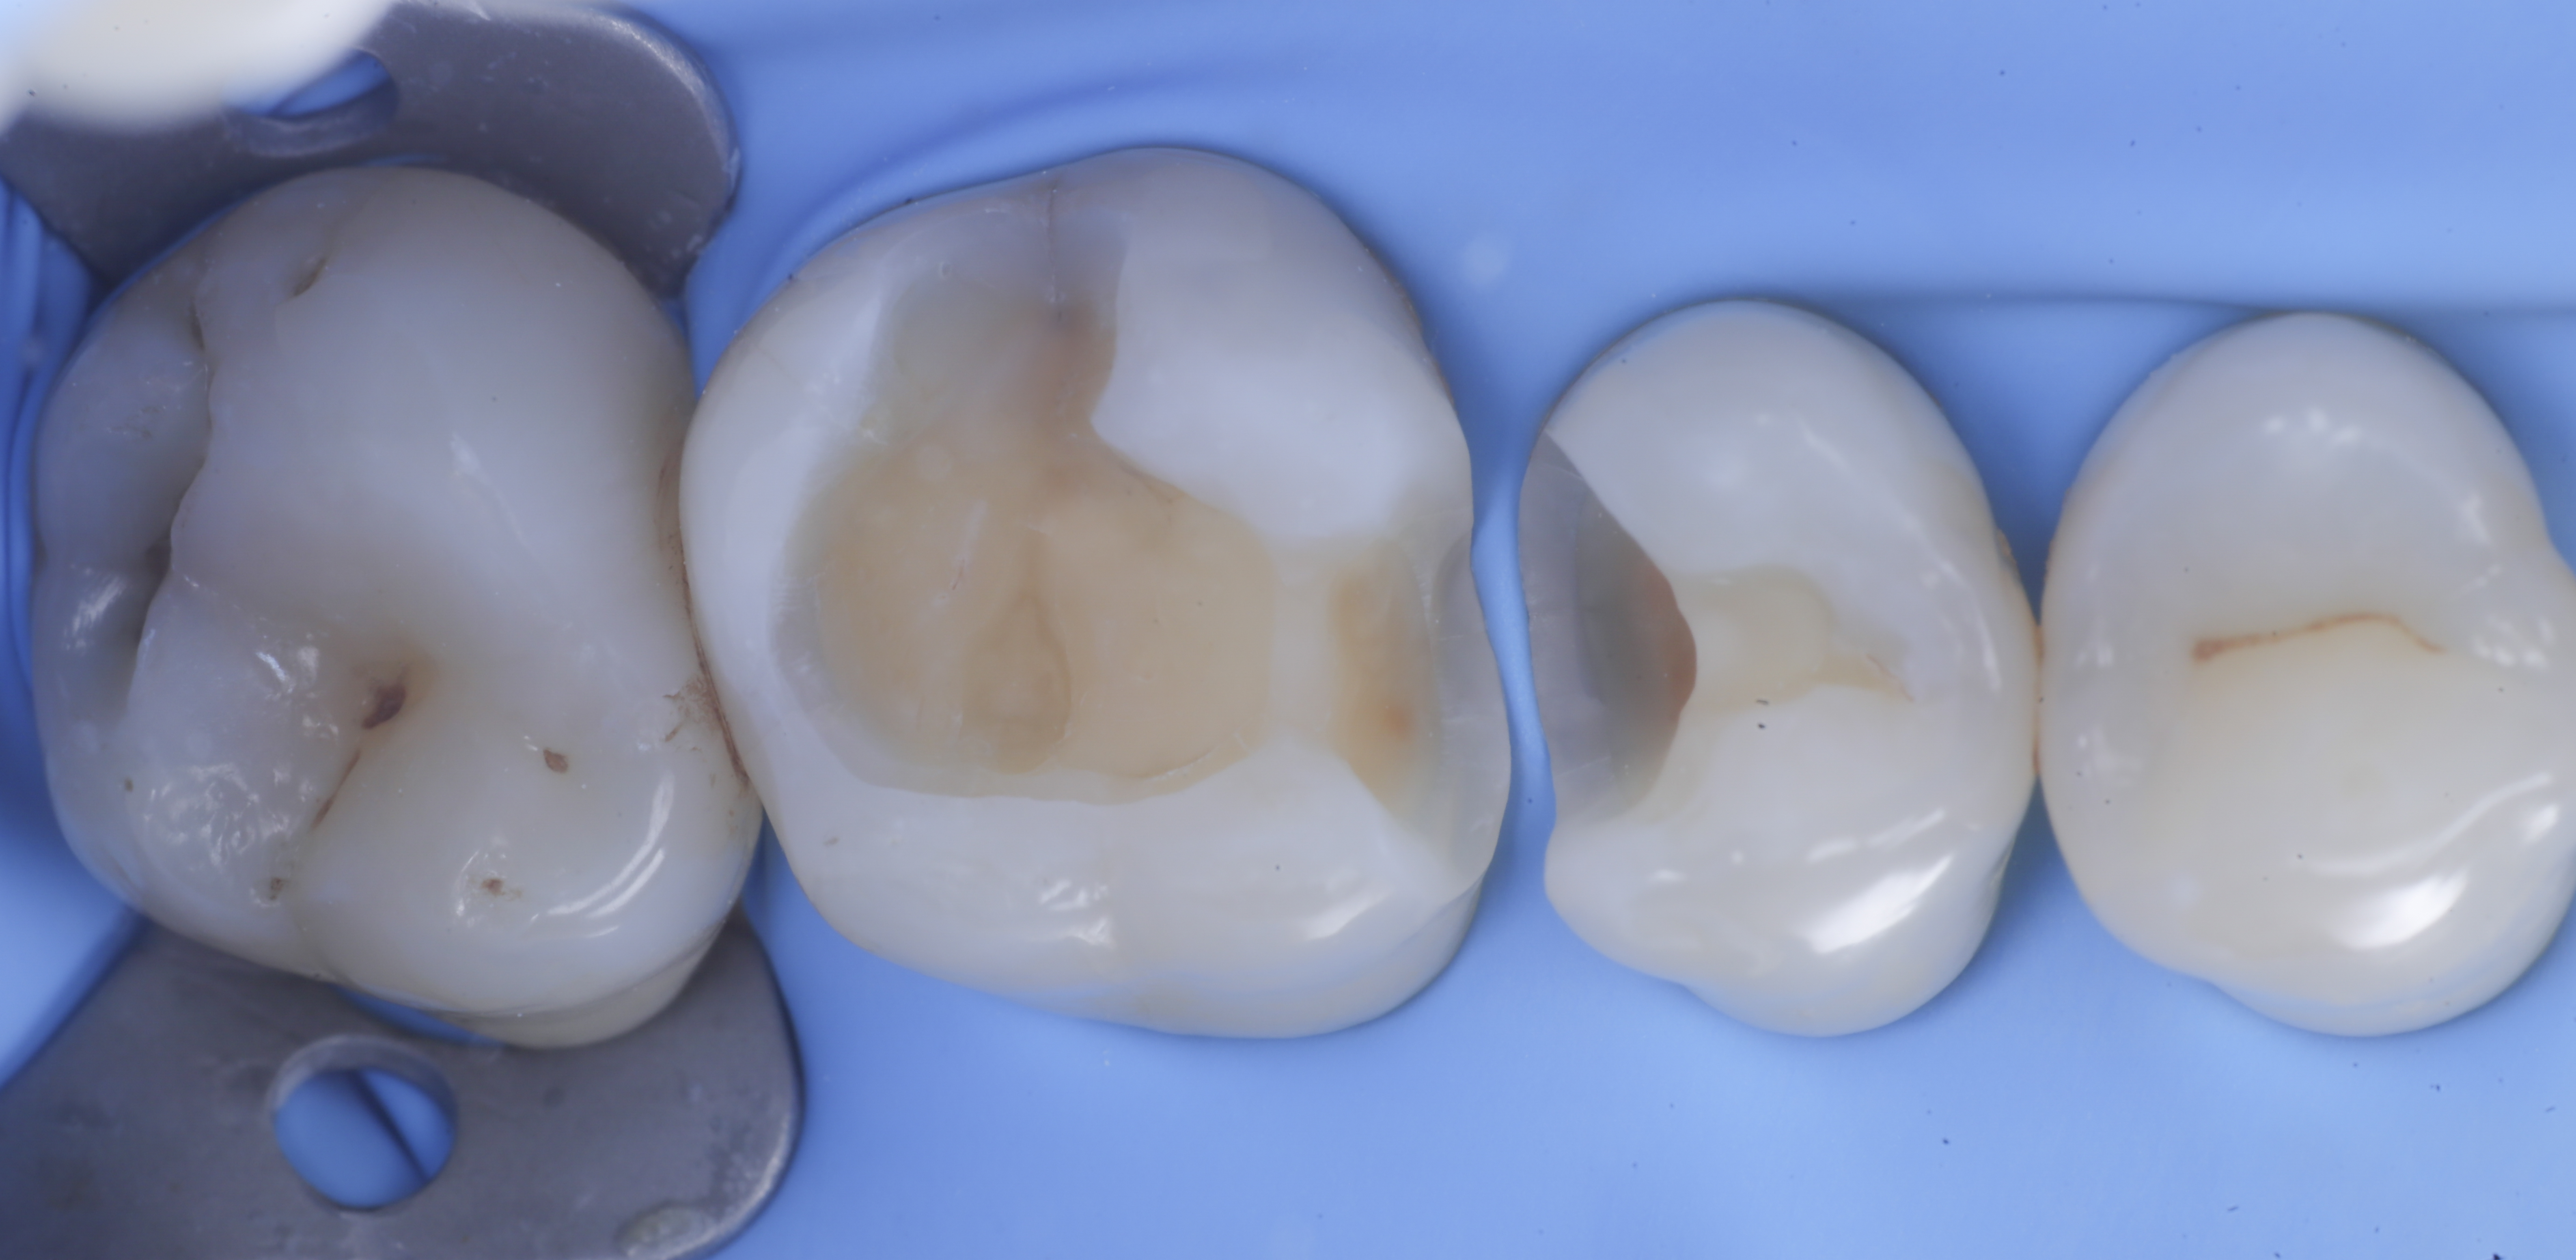

foto 4 Aspetto della chiusura cervicale e sulle pareti assiali dato dalla prima matrice

foto 5 Aspetto della chiusura cervicale e sulle pareti assiali della seconda matrice